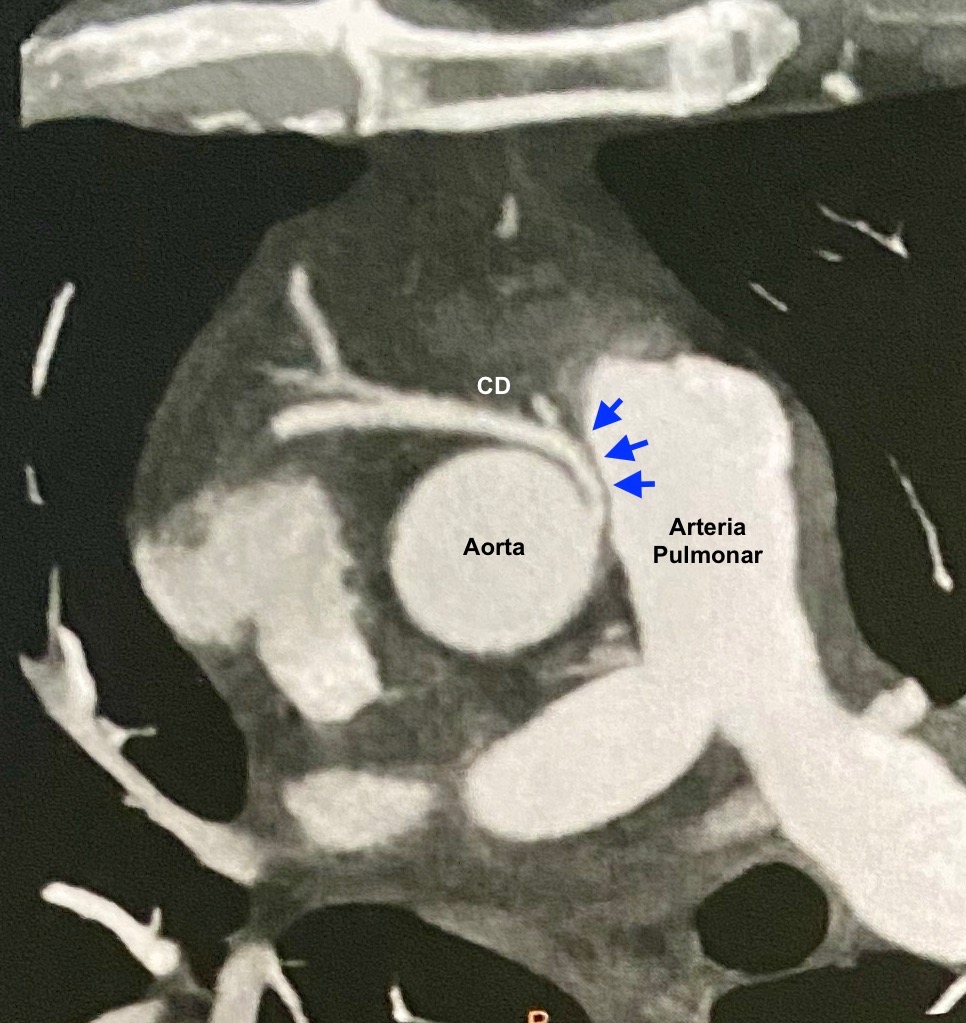

Presentamos el caso de un varón de 67 años de edad y múltiples factores de riesgo cardiovascular (dislipémico, diabético y exfumador), que acude a su cardiólogo del Hospital Vithas Pardo de Aravaca por dolor retroesternal al subir cuestas con sensación de taquicardia acompañante, que cedía con le reposo. La ergometría fue clínicamente positiva al presentar angina desde el minuto 2 de ejercicio. En el TAC de coronarias se objetivó el nacimiento anómalo superior de la coronaria derecha en el seno de Valsalva izquierdo, muy cerca a la unión con el seno derecho, existiendo un trayecto interarterial. Además, tanto la descendente anterior como la circunfleja presentaban placas no significativas del 30% y 40%, respectivamente.